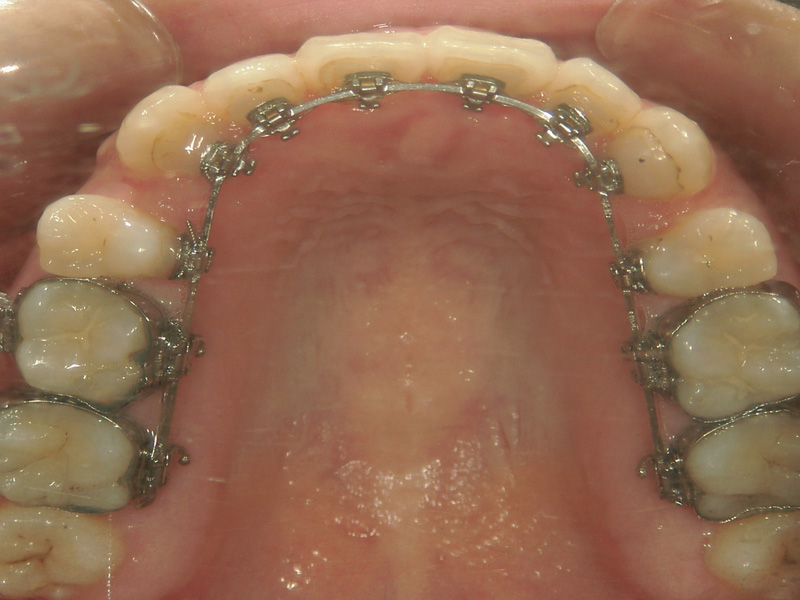

ハーフリンガル(上顎:舌側、下顎:唇側)

見えやすい上顎は裏側、目立ちにくい下顎は表側にブラケットとワイヤー を装着する方法です。

処置時間の短縮、装置の不快感の軽減、衛生管理のしやすさの向上が図れます。治療規則は舌側矯正に則り、平日午前中のみの対応となります。